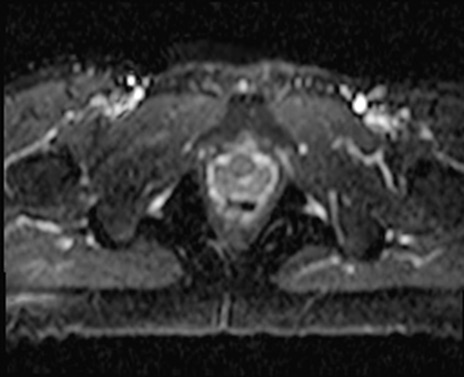

症例39 DWI/ADC

MRI(4日後)